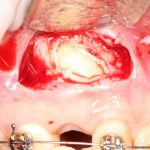

Иссечение воспаленной десны над зубом (того самого «капюшона), с последующей обработкой и дренажем образовавшейся раны.

Такая тактика оправдана в случае, если:

— по данным рентгенодиагностики (КЛКТ или ортопантомограммы) зуб находится в стадии прорезывания (верхушки корней не сформированы), ось прорезывания зуба имеет более-менее правильное направление, его коронковая часть не повреждена кариесом.

— врач-ортодонт подтверждает, что для прорезывания третьего моляра есть необходимое пространство (хватит места в зубном ряду), нет патологии прикуса и признаков развивающейся зубочелюстной аномалии.

— подобное состояние (перикоронит) у тебя впервые, и ты раньше никогда с ним не сталкивался.

— тебе не больше 20 лет.

При совпадении всех четырех условий, КОМПЕТЕНТНЫЙ хирург-стоматолог с помощью скальпеля иссечет десну над коронковой частью прорезывающегося зуба, остановит кровотечение, дренирует образовавшуюся рану, сделает послеоперационные назначения (как правило, они включают в себя антибактериальную и противовоспалительную терапию, а также уход за областью послеоперационной раны) и запишет тебя на послеоперационные осмотры, которые ни в коем случае нельзя игнорировать.

Если всё норм, и показания к хирургическому вмешательству ты и врач определили правильно — твой злосчастный зуб прорежется и займет своё место в зубном ряду. Тебе лишь останется за ним ухаживать, периодически показываясь стоматологу на профилактических осмотрах.